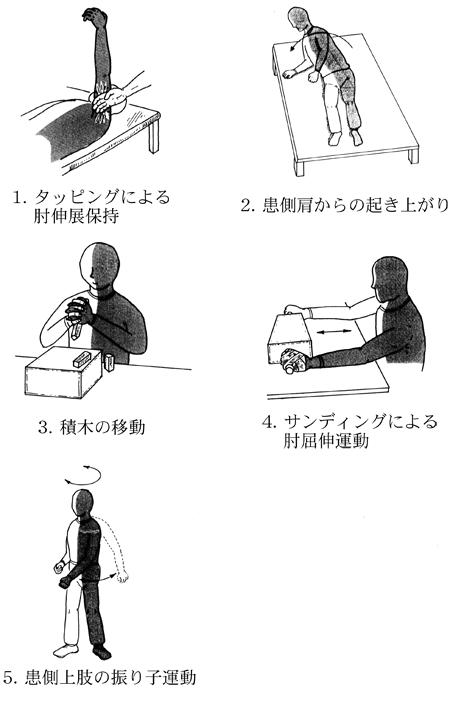

60歳の男性。左片麻痺。脳梗塞発症後1か月経過。認知機能や感覚機能に問題はない。ブルンストローム法ステージは上肢II、下肢V。上肢運動機能の回復促進で適切でないのはどれか。

1

1

2

2

3

3

4

4

5

5

発症後2か月の脳卒中右片麻痺患者。上肢ブルンストローム法ステージIV。上肢の伸筋群に随意的な関節運動が認められるようになった。肘伸展を誘発するための治療的活動で適切でないのはどれか。

1

1

2

2

3

3

4

4

5

5

68歳の女性。発症後2か月の脳卒中右片麻痺患者。Brunnstrom法ステージは上肢Ⅳ。上肢の伸筋群に随意的な関節運動が認められるようになった。肘伸展を誘発するための作業療法で適切でないのはどれか。

1

1

2

2

3

3

4

4

5

5